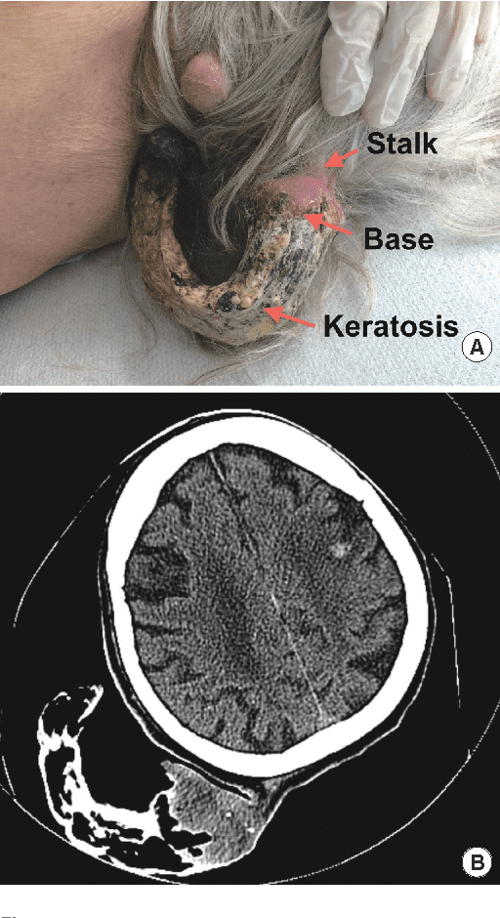

Figure 1 from A Pedunculated Giant Cutaneous Horn Variant Overlying

Figure 1 from A Pedunculated Giant Cutaneous Horn Variant Overlying Horn Cancer Definition A cutaneous horn, or cornu cutaneum, is a relatively uncommon, hyperkeratotic epithelial lesion resembling an animal horn, characterized by a height more than half of the. A cutaneous horn is diagnosed by its clinical appearance. A skin horn (also known as a cutaneous horn or cornu cutaneum) is a lesion that resembles an animal horn. Histological examination of the horn. Horn Cancer Definition.